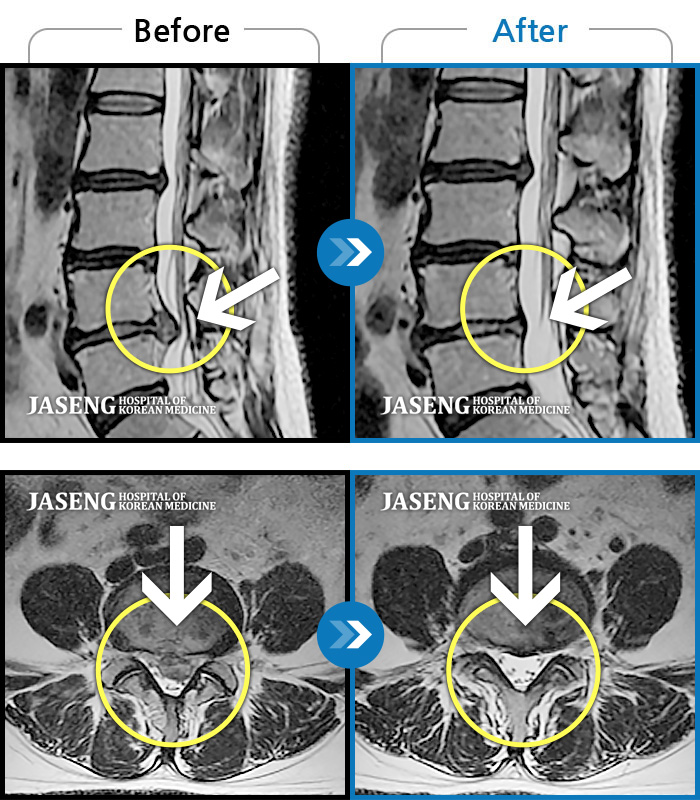

제가 가지고 간 MRI 영상자료를 보시면서 수술하지 않고도 충분히 고칠수 있다는 희망적인 말과 증상에 대해 자세히 설명해주시고 앞으로 어떻게 치료할 것인지에 대하여 알기쉽게 설명해주셔서 감사했습니다.